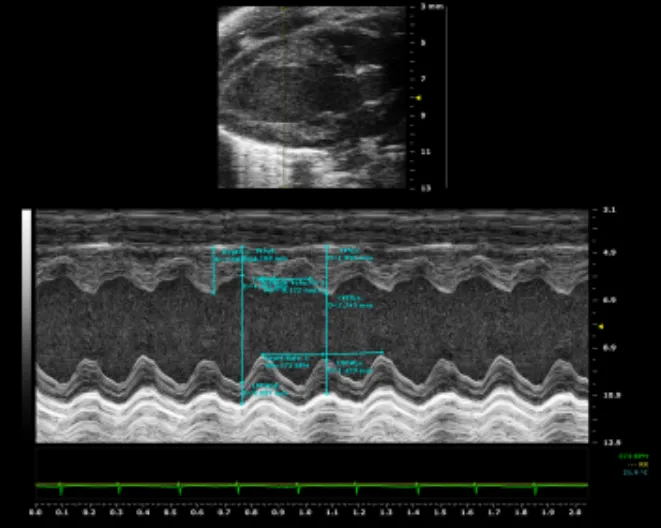

超声成像具有实时、动态的特点,能够观察软组织的结构变化,设备便携、无辐射风险,在心血管和胚胎发育研究中优势明显。